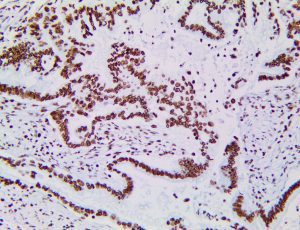

It is the ICU physician who is most likely to witness one of the deadliest manifestations of the abnormal immunological response, the cytokine storm syndrome (CSS). This response is also referred to by some as the cytokine release syndrome (CRS). CSS is characterized by continuous activation and expansion of macrophage and lymphocyte populations, which secrete large amounts of cytokines, causing the cytokine storm. This massive cytokine release is akin to hemophagocytic lymphohistiocytosis (HLH) disease, a syndrome characterized by initial unchecked and persistent activation of cytotoxic T lymphocytes and NK cells.

Clinical and laboratory manifestations of HLH include fever, enlarged liver and/or spleen, neurologic dysfunction, coagulopathy, liver dysfunction, cytopenias (i.e., low levels of erythrocytes, leukocytes, and/or platelets), hypertriglyceridemia, hyperferritinemia, hemophagocytosis, and eventually diminished NK cell activity as the immune system becomes progressively paralyzed. HLH can be familial (primary HLH) or secondary to another disease process (sHLH), such as rheumatic disease, in which it is referred to as macrophage activation syndrome (MAS, characterized by elevated ferritin).